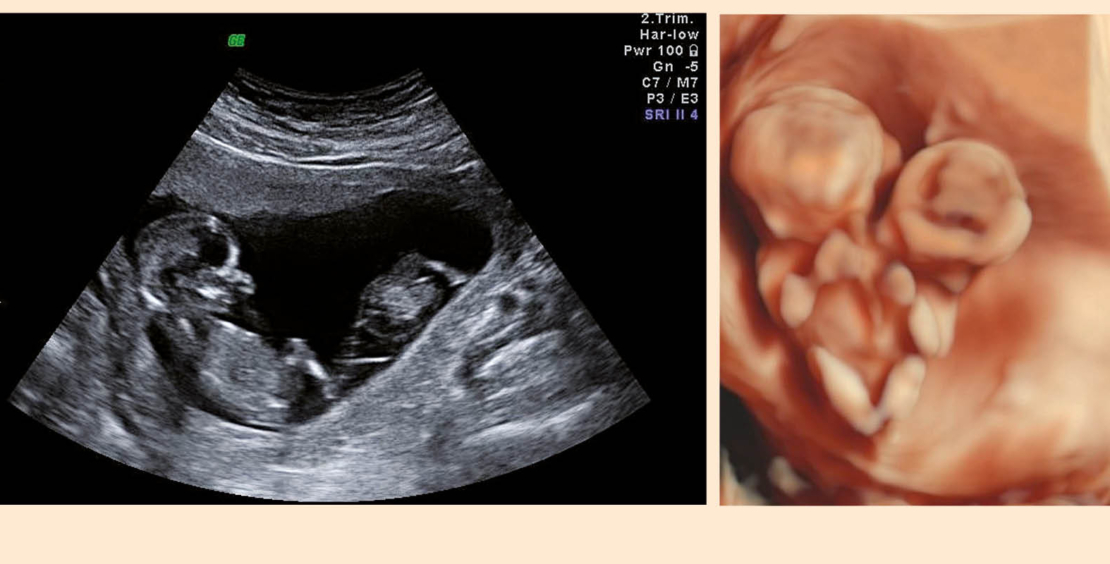

Teilt sich die Zygote erst nach dem 13. Tag post conceptionem, resultieren siamesische Zwillinge (Abb. 3a). Art und Ausmass der Verbindung kann sehr variieren und geht entsprechend mit unterschiedlichsten Prognosen einher. Wichtig sind eine frühzeitige Diagnose und eine entsprechende Beratung des Paares.